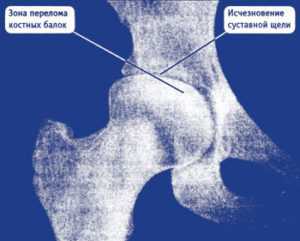

Снимок 2. Пациент обратился к врачу по поводу боли в правом паху и правом бедре, возникающей только при ходьбе или вставании со стула.

Коксартроз 2-й стадии. Фотография из архива доктора Евдокименко

Вот что мы видим на снимке пациента:

- головка бедренной кости «подтянулась» к вертлужной впадине, расстояние между костями совсем небольшое (уменьшение размеров суставной щели). Это говорит о том, что суставной хрящ, покрывающий сочленяющиеся части костей, стал гораздо тоньше (как вы помните, на рентгене сам хрящ не виден);

- оставшись без «хрящевого амортизатора», головка бедренной кости стала деформироваться, частично расплющиваться. Она теперь не такая идеально-круглая, как должна быть.

Такие рентгенологические изменения соответствуют коксартрозу второй стадии.

Снимок 3. Здесь представлен снимок пациентки, которой диагноз «коксартроз» поставили вовремя, еще на первой стадии болезни. Но, несмотря на своевременно поставленный серьезный диагноз, сама пациентка очень безалаберно отнеслась к своему здоровью и 5 лет игнорировала назначенное врачами правильное лечение. Вот что представлял ее сустав через 5 лет:

- суставной хрящ разрушен почти полностью (нет расстояния между костями, головка бедренной кости почти полностью «вклинилась» в вертлужную впадину);

- головка бедренной кости сильно деформирована, цвет верхней части головки на рентгене выглядит светлее (признак микроперелома костных балок из-за повышенного давления на верхнюю часть головки).

Коксартроз 3-й стадии. Фотография из архива доктора Евдокименко

Все эти рентгенологические признаки соответствуют коксартрозу третьей стадии. Третья стадия коксартроза была также подтверждена во время осмотра пациентки. К сожалению, из-за того, что пациентка халатно отнеслась к своему здоровью и не стала лечиться вовремя, ей пришлось идти на операцию по замене тазобедренного сустава.